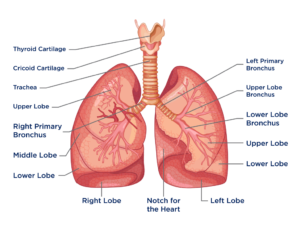

LUNGS:

The lungs work with the heart to oxygenate blood. They do this by filtering the air a person breathes, then removing excess carbon dioxide in exchange for oxygen.

Several parts of the lungs help the body take in air, filter it, and then oxygenate the blood. These are:

The left and right bronchi: The trachea splits into these tubes, which extend into the lungs and have branches. These smaller bronchi split into even smaller tubes called bronchioles.

The alveoli: The alveoli are tiny air sacs at the end of the bronchioles. They work like balloons, expanding when a person inhales and contracting when they exhale.

The blood vessels: There are numerous blood vessels in the lungs for carrying blood to and from the heart.

With extensive medical care, a person can live without one lung, but they cannot survive with no lungs.

The diaphragm, which is a thick band of muscle directly under the lungs, helps the lungs expand and contract when a person breathes.